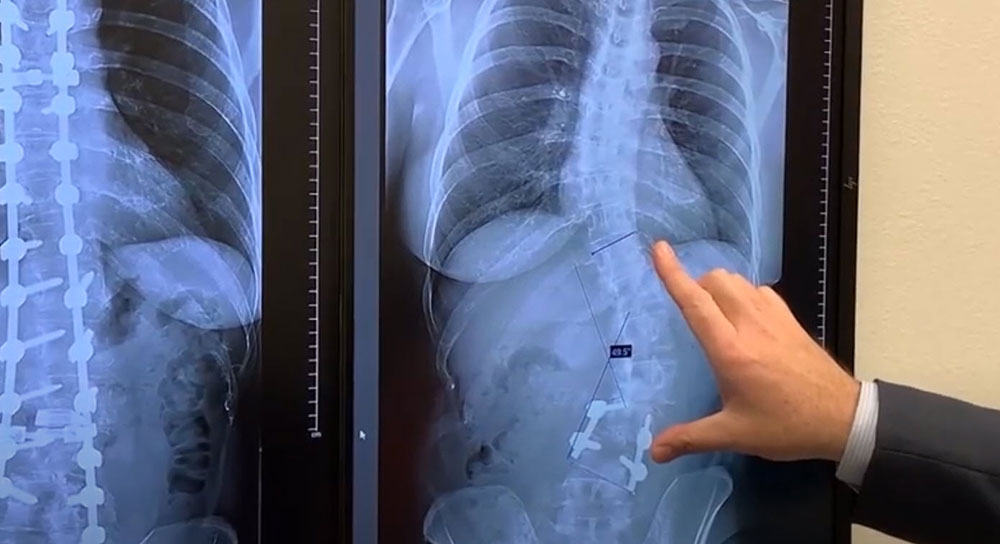

Dr. Taggard says Wahlenmaier had a mild spinal deformity called degenerative scoliosis, also known as adult scoliosis.

Adult scoliosis is the rotation and curvature of the spine. Naturally, the spine has a forward and a backward curve, but with scoliosis, it rotates and develops a side-to-side curve. Any sideways spinal curve of at least 10 degrees is considered scoliosis. Dr. Taggard says that about 10% of the population has some degree of scoliosis.